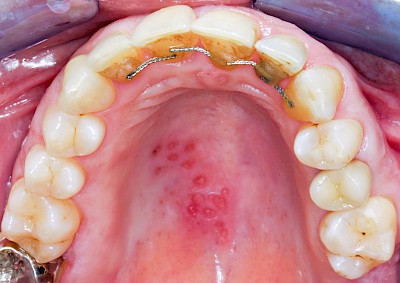

Herpes-Bläschen können ebenfalls kleine Gruppierungen von Bläschen zeigen, die dann aber – zumindest zu Beginn – streng auf einer Seite lokalisiert sind. Herpes-Viren ziehen sich nach Erstinfektion in bestimmte Strukturen der Nerven-Gewebe (Spinalganglien) zurück und können unter besonderen Bedingungen (nach Stress-Situationen, nach Sonnenexposition...) wieder "ausbrechen". Herpes-simplex Viren zeigen sich bei vielen Menschen an den Lippen. Seltener sind Schleimhautbereiche im Mund (am ehesten noch der Gaumen) betroffen. Manchmal sind auch Herpes-Zoster-Viren die Ursache.

Beispiele13 Bilder